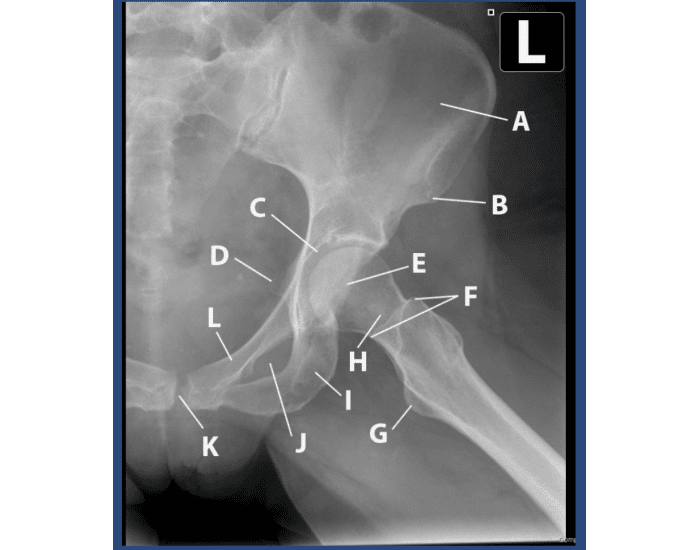

What anatomy is included in the AP pelvis projection?

Pelvic girdle, L5, sacrum, coccyx, femoral heads & neck, and greater trochanters.

What is the CR location for the hip projections?

a. ASIS

b. Greater trochanter

c. Femoral neck

d. Iliac crest

Femoral neck (1-2 inches medial & 3-4 inches distal to ASIS)

Which structures on an AP pelvis or hip radiograph indicate whether the proximal head and neck are in position for a true AP projection?

Lesser trochanter should not be visible